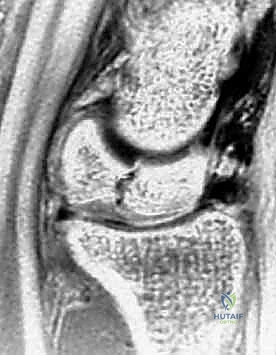

العظم الهلالي (Lunate Bone): حجر الزاوية

يقع العظم الهلالي في الصف القريب، محصوراً بين العظم الزورقي (Scaphoid) والعظم المثلثي (Triquetrum). سُمي بالهلالي نظراً لشكله الذي يشبه الهلال. وظيفياً، يلعب العظم الهلالي دوراً محورياً في توزيع القوى الميكانيكية (الأحمال) من اليد إلى الساعد. يُقدر أن حوالي 50% من القوة الضاغطة التي تعبر الرسغ تمر مباشرة عبر العظم الهلالي إلى عظمة الكعبرة.

- التصوير بالرنين المغناطيسي (MRI): هو المعيار الذهبي للتشخيص المبكر. يمكن للرنين المغناطيسي اكتشاف نقص التروية الدموية (وذمة العظم) قبل أشهر من ظهور أي تغيرات في الأشعة السينية. يعتمد الدكتور هطيف بشكل كبير على الرنين المغناطيسي لتحديد مرحلة المرض بدقة.

| المرحلة الثانية (Stage II) | الأشعة السينية تظهر العظم الهلالي أكثر بياضاً (تصلب). العظم لا يزال محتفظاً بشكله العام ولكن قد تظهر خطوط كسر دقيقة. | جراحة لتفريغ الضغط أو زراعة طعم وعائي. |

| المرحلة الثالثة أ (Stage IIIA) | انهيار وتفلطح العظم الهلالي. تفتت الأجزاء. لا يوجد انهيار في ارتفاع عظام الرسغ الكلية. | زراعة طعم عظمي وعائي + جراحة تسوية المفصل (تقصير العظم الكبير أو تطويل الكعبرة). |